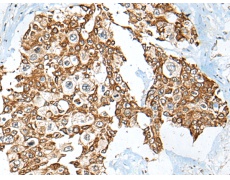

ELISA, IHC |

IHC positive control: |

Human thyroid cancer and human prostate cancer |

IHC Recommend dilution: |

30-150 |